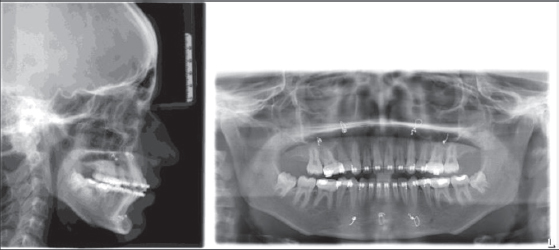

Based on the research by Anyanechi et al.[24] and Will et al.[25] it has been suggested that wire osteosynthesis is capable of sustaining forces and movements during the wire fixation period, facilitating the alignment of the callus and enabling the teeth to accommodate minor skeletal changes. This indicates that in current practice, this method may continue to be valuable, especially in settings with limited access to rigid internal fixation equipment. Van Sickels[26] reported that in rigid fixation, there are more occlusion-related problems as compared with those with wire osteosynthesis. The comparison of the two groups I (wire fixation, Figure 10) and II (rigid fixation, Figure 11) revealed that skeletally both groups I and II had a relapse in the 6-month postoperative period but not to a significant level. Group I had more relapse than Group II in the posterior maxilla.

thumb

Figure 10: Group I (wire osteosynthesis) preoperative and postoperative

Figure 11: Group II (rigid osteosynthesis) preoperative and postoperative